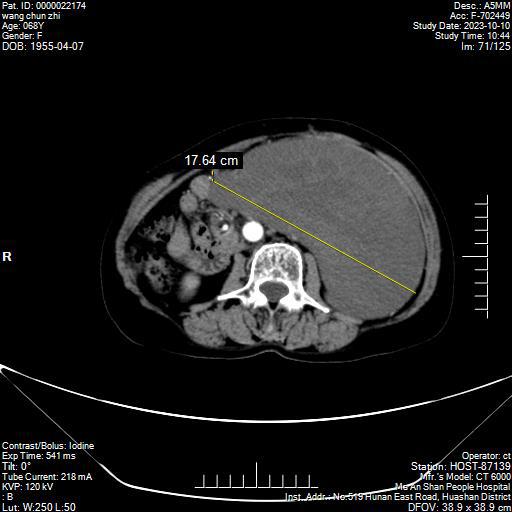

2023年9月,68歲的王女士覺得腹部越來越大,開始以為年齡大、體重增加造成的腹圍大。漸漸地,王女士感覺左側(cè)腹部鼓起來了,還伴有脹痛感,遂來到市人民醫(yī)院東院普外綜合科就診。CT檢查顯示王女士腹膜巨大占位,最長徑約30cm,已經(jīng)壓迫脾臟和左腎,推擠大、小腸。必須盡快手術(shù)治療才是最好的辦法。

10月23日,普外綜合科手術(shù)團(tuán)隊為王女士實施了腹膜后巨大脂肪瘤切除術(shù),經(jīng)過2個多小時的緊張忙碌,手術(shù)團(tuán)隊完整取出一枚30*19*9cm巨大的腫瘤。術(shù)后病理檢測結(jié)果為脂肪肉瘤。目前王女士恢復(fù)順利已痊愈出院。